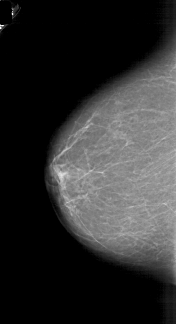

A_1718_1.LEFT_CC

LEFT_CC LINES 5821 PIXELS_PER_LINE 3166 BITS_PER_PIXEL 12 RESOLUTION 43.5 NON_OVERLAY